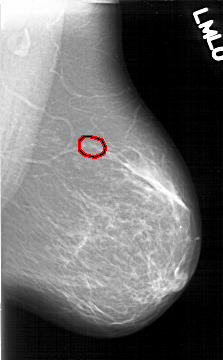

D_4195_1.LEFT_MLO

LEFT_MLO LINES 6466 PIXELS_PER_LINE 4006 BITS_PER_PIXEL 12 RESOLUTION 43.5 OVERLAY

FILE: D_4195_1.LEFT_MLO.OVERLAY

TOTAL_ABNORMALITIES 1

ABNORMALITY 1

LESION_TYPE CALCIFICATION TYPE AMORPHOUS DISTRIBUTION CLUSTERED

ASSESSMENT 0

SUBTLETY 3

PATHOLOGY BENIGN

TOTAL_OUTLINES 1

BOUNDARY